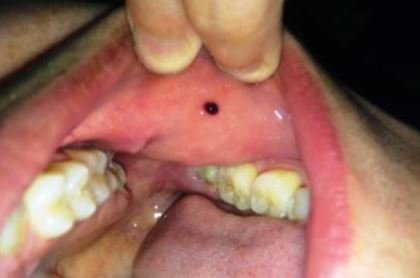

Pictures of blood blisters inside cheek

Appearance of the blood blister in the mouth cheek may be of different size or may have varying degree of redness for different people. The doctor observes the blood blister before carrying out further tests. The way the blister appears is always a hint on the probable cause of that blister and perhaps the severity. Below are some pictures of blood blisters inside the mouth cheek: